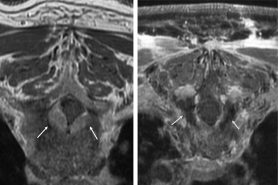

Para el paso de la ablación, se inserta una sonda láser hasta el extremo de la cánula de acceso en el tumor, y la cánula se retrae ligeramente para exponer la punta de la sonda láser. La sonda entonces se energiza para calentar el tejido circundante a una temperatura que daña irreversiblemente las células tumorales (por lo general, de 50 a 74 °C); la temperatura en la separación entre el tumor y las estructuras vitales se mantiene a menos de 50 °C para evitar el daño a estas últimas. El proceso de calentamiento es monitoreado en tiempo real con termometría por MRI.

“Lo que hace que este procedimiento sea especial no es la temperatura misma, sino el monitoreo de la temperatura en el espacio”, dijo el Dr. Tatsui. “La MRI me permite localizar la temperatura y tratar lesiones cercanas a órganos vitales sin dañar esas estructuras. Podemos verificar en tiempo real adónde se está aplicando calor, la extensión del daño y si es preciso colocar sondas láser adicionales”.